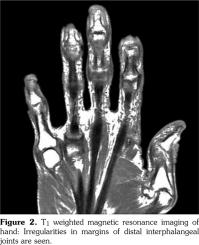

A complete blood count, electrolyte, and acute phase reactant tests revealed no abnormalities. Rheumatologic markers including the rheumatoid factor and anti‐citrullinated antibody were all negative. Direct radiography revealed an evidence of intraarticular erosion, periosteal reaction, and prominent thickened periarticular and paraosseous soft tissues (Figure 1). A magnetic resonance imaging of the hands showed irregularities of the DIP joints in T1 weighted images (Figure 2). Based on the findings mentioned above, the patient was diagnosed as having POPP. The patient was started on methylprednisolone 5 mg/day and methotrexate 10 mg/week, which increased to 15 mg/week after two weeks. The patient was evaluated after four weeks of treatment and liver function tests; the creatinine and complete blood counts were normal and there was an 80% improvement in the pain scores (10 cm visual analog scale) for arthralgia. The patient was re‐ evaluated after three months of treatment and there was a 90% improvement in the pain scores compared to the scores at admission and new nail formations at the base of the nail beds were observed.

Radiographic findings in POPP include intra‐ and periarticular erosions, new bone formation including periostitis, bony protuberances, soft tissue prominence (dactylitis or sausage digits), and calcification at ligament and tendinous insertions in keeping with enthesopathy.(9) Sanal et al.(10) described a case of POPP with extensive bone marrow edema of the metacarpal bones without distinctive periostitis.